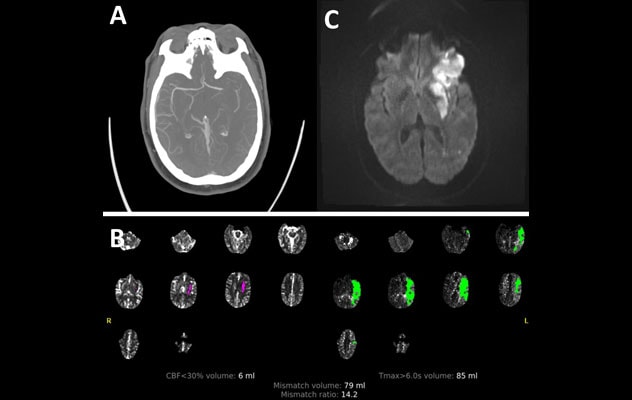

A 38-year-old woman who was previously healthy awoke with dense right hemiplegia and aphasia. A. CT angiogram showed left middle cerebral artery occlusion. B. CT perfusion showed an ischemic penumbra of potentially salvageable tissue. The patient underwent thrombolysis in cerebral infarction 2b recanalization. C. MRI of the brain at discharge showed ischemic infarct over the left inferior frontal lobe and lentiform. Head and neck angiogram showed no steno-occlusive disease, and hypercoagulable work-up was unremarkable. The patient was referred to the Heart Brain Clinic for comprehensive evaluation. Echocardiogram revealed a PFO with atrial septal aneurysm. The stroke etiology was determined to be paradoxical embolic secondary to the PFO. The patient underwent successful PFO closure.